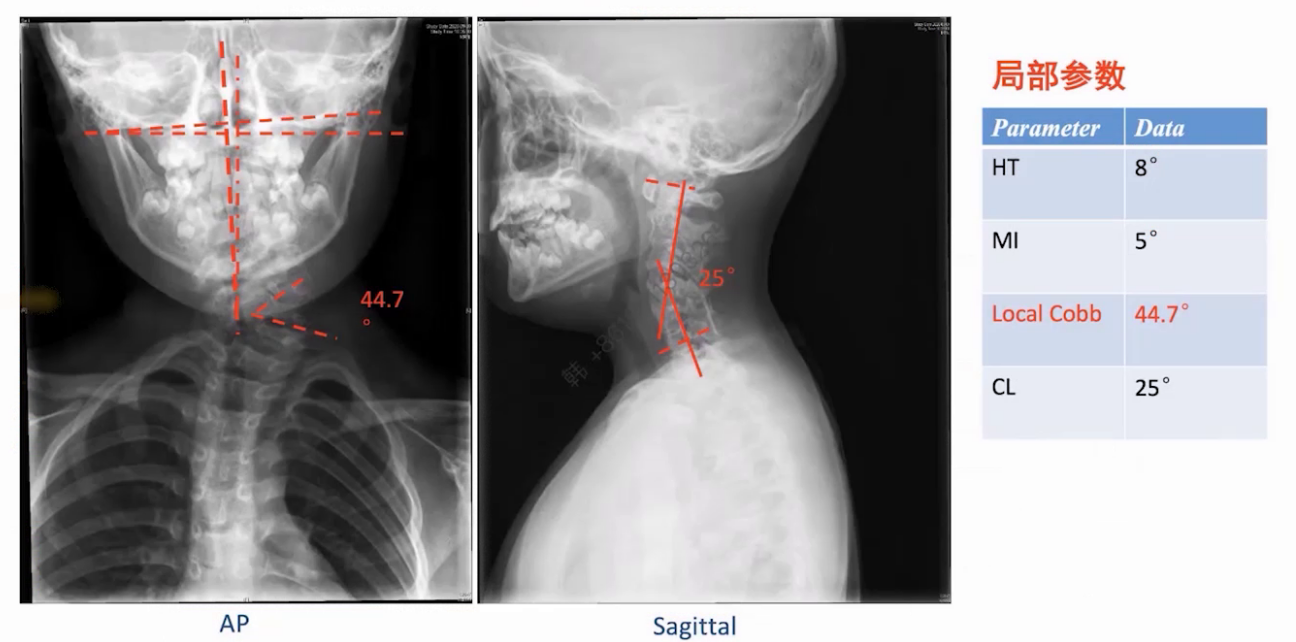

脊柱全长X线显示C4-T1侧弯角度57.7度,双肩高度差2.8cm,冠状位和矢状位基本平衡;局部参数显示半椎体畸形角度达44.7度,颈椎后凸角度25度,颈部活动度正常。